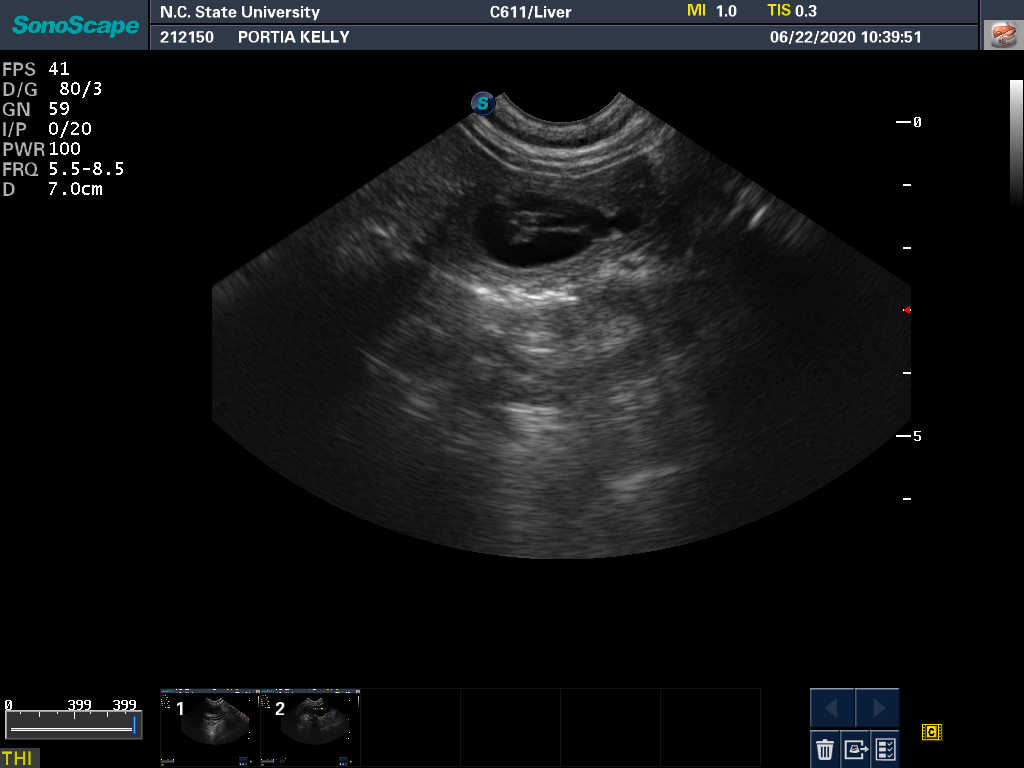

22 Jun

Ultrasound today by the theriogenology (reproduction) vets at NC State University showed the Portia is pregnant with most likely one puppy. It can be difficult to accurately count puppies using ultrasound - so there could be more than one puppy - but there is at least one puppy with a good heart beat.

The bad news is that the ultrasound also revealed an absorption site. Dogs absorb, rather than have miscarriages. So my repro vets are treating this as a "problem" pregnancy. Portia has been put on the drug terbutaline to "calm her uterus". We will be coming back to NC State for repeated ultasounds on a regular basis during the pregnancy.